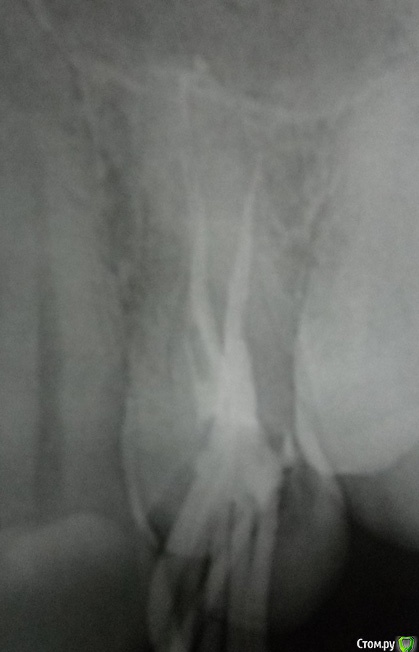

regi Опубликовано 24 февраля, 2016 Поделиться Опубликовано 24 февраля, 2016 (изменено) Сегодня мне начали лечение зуба. Пока только прошли каналы и поставили временную пломбу.В настоящий момент при надавливании на зуб чувствуется острая боль.Решил поизучать внимательно снимок и обнаружил внутри канала обломок. Врачу снимок еще не показывал (должен принести на следующий приём).На что следует обратить внимание при дальнейшем общении с врачом? Следует ли настаивать на удалении обломка? Клиника государственная, поэтому опасаюсь, что могут оставить как есть, по типу "и так сойдёт". Изменено 24 февраля, 2016 пользователем regi Ссылка на комментарий

regi Опубликовано 25 февраля, 2016 Автор Поделиться Опубликовано 25 февраля, 2016 Сегодня принёс врачу снимок, она сказала что всё вроде как отлично. Я пожаловался на боль и указал на осколок на снимке, она вообще тоже заявила, что это нормально, потом отправила на повторную рентегографию на радиовизиографе. Честно говоря, на мой непрофессиональный взгляд все выглядит еще хуже, чем казалось. Прикидываю длину осколка, получается сантиметра полтора? Край очень близко к стенке корня, возможна перфорация? Врач согласилась завтра вытащить осколок, хотя я теперь реально сомневаюсь, стоит ли продолжать лечение у неё, или будет только хуже. Я так понимаю по вашим ответам, что пломбирование каналов тоже некачественное и требует переделки? Уважаемый, цели форума несколько иные, наша помощь лежит сугубо в медицинской плоскости. Прошу прощения. Я понимаю, что с этической стороны некоторые вопросы не самые приятные. Но я их задаю только потому, что хочу как раз получить надлежащую медицинскую помощь. Одно дело, если врач ошибся ненамеренно, и совсем другое, если недобросовестно подходит к своим обязанностям. Ссылка на комментарий